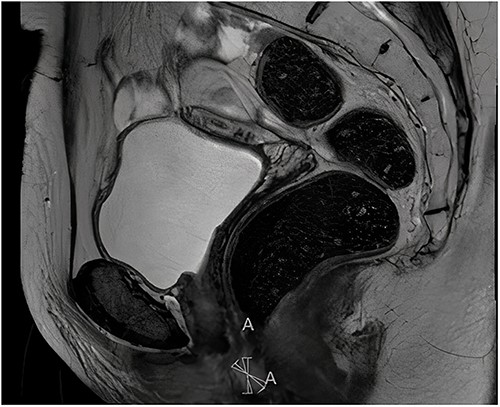

Histopathological examination of the biopsy showed an adenocarcinoma metastasis of rectal origin. A full body positron emission tomography (PET)-scan and MRI were made and confirmed the vaginal lesion of 1.7 × 1.4 × 1.5 cm located in the posterior wall of the vagina just above the puborectal sling (see Figs 1 and 2). From the histopathological and imaging diagnostics we concluded that the patient had a distal rectovaginal septum metastasis of rectal origin.

Sagittal view of diagnostic MRI-rectum with the solid tumour indicated with the linear mark ‘A’.